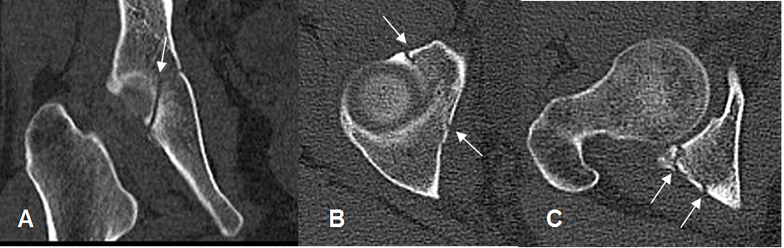

Fig 57. Fractura de acetábulo. Igual paciente anterior.

A: TAC reconstrucción coronal. Fractura oblicua, del techo acetabular.

B: TAC axial. Fractura en la parte anterior y posterior del techo acetabular.

C: TAC axial. Subluxación de la cabeza femoral, con fractura conminuta del reborde posterior.